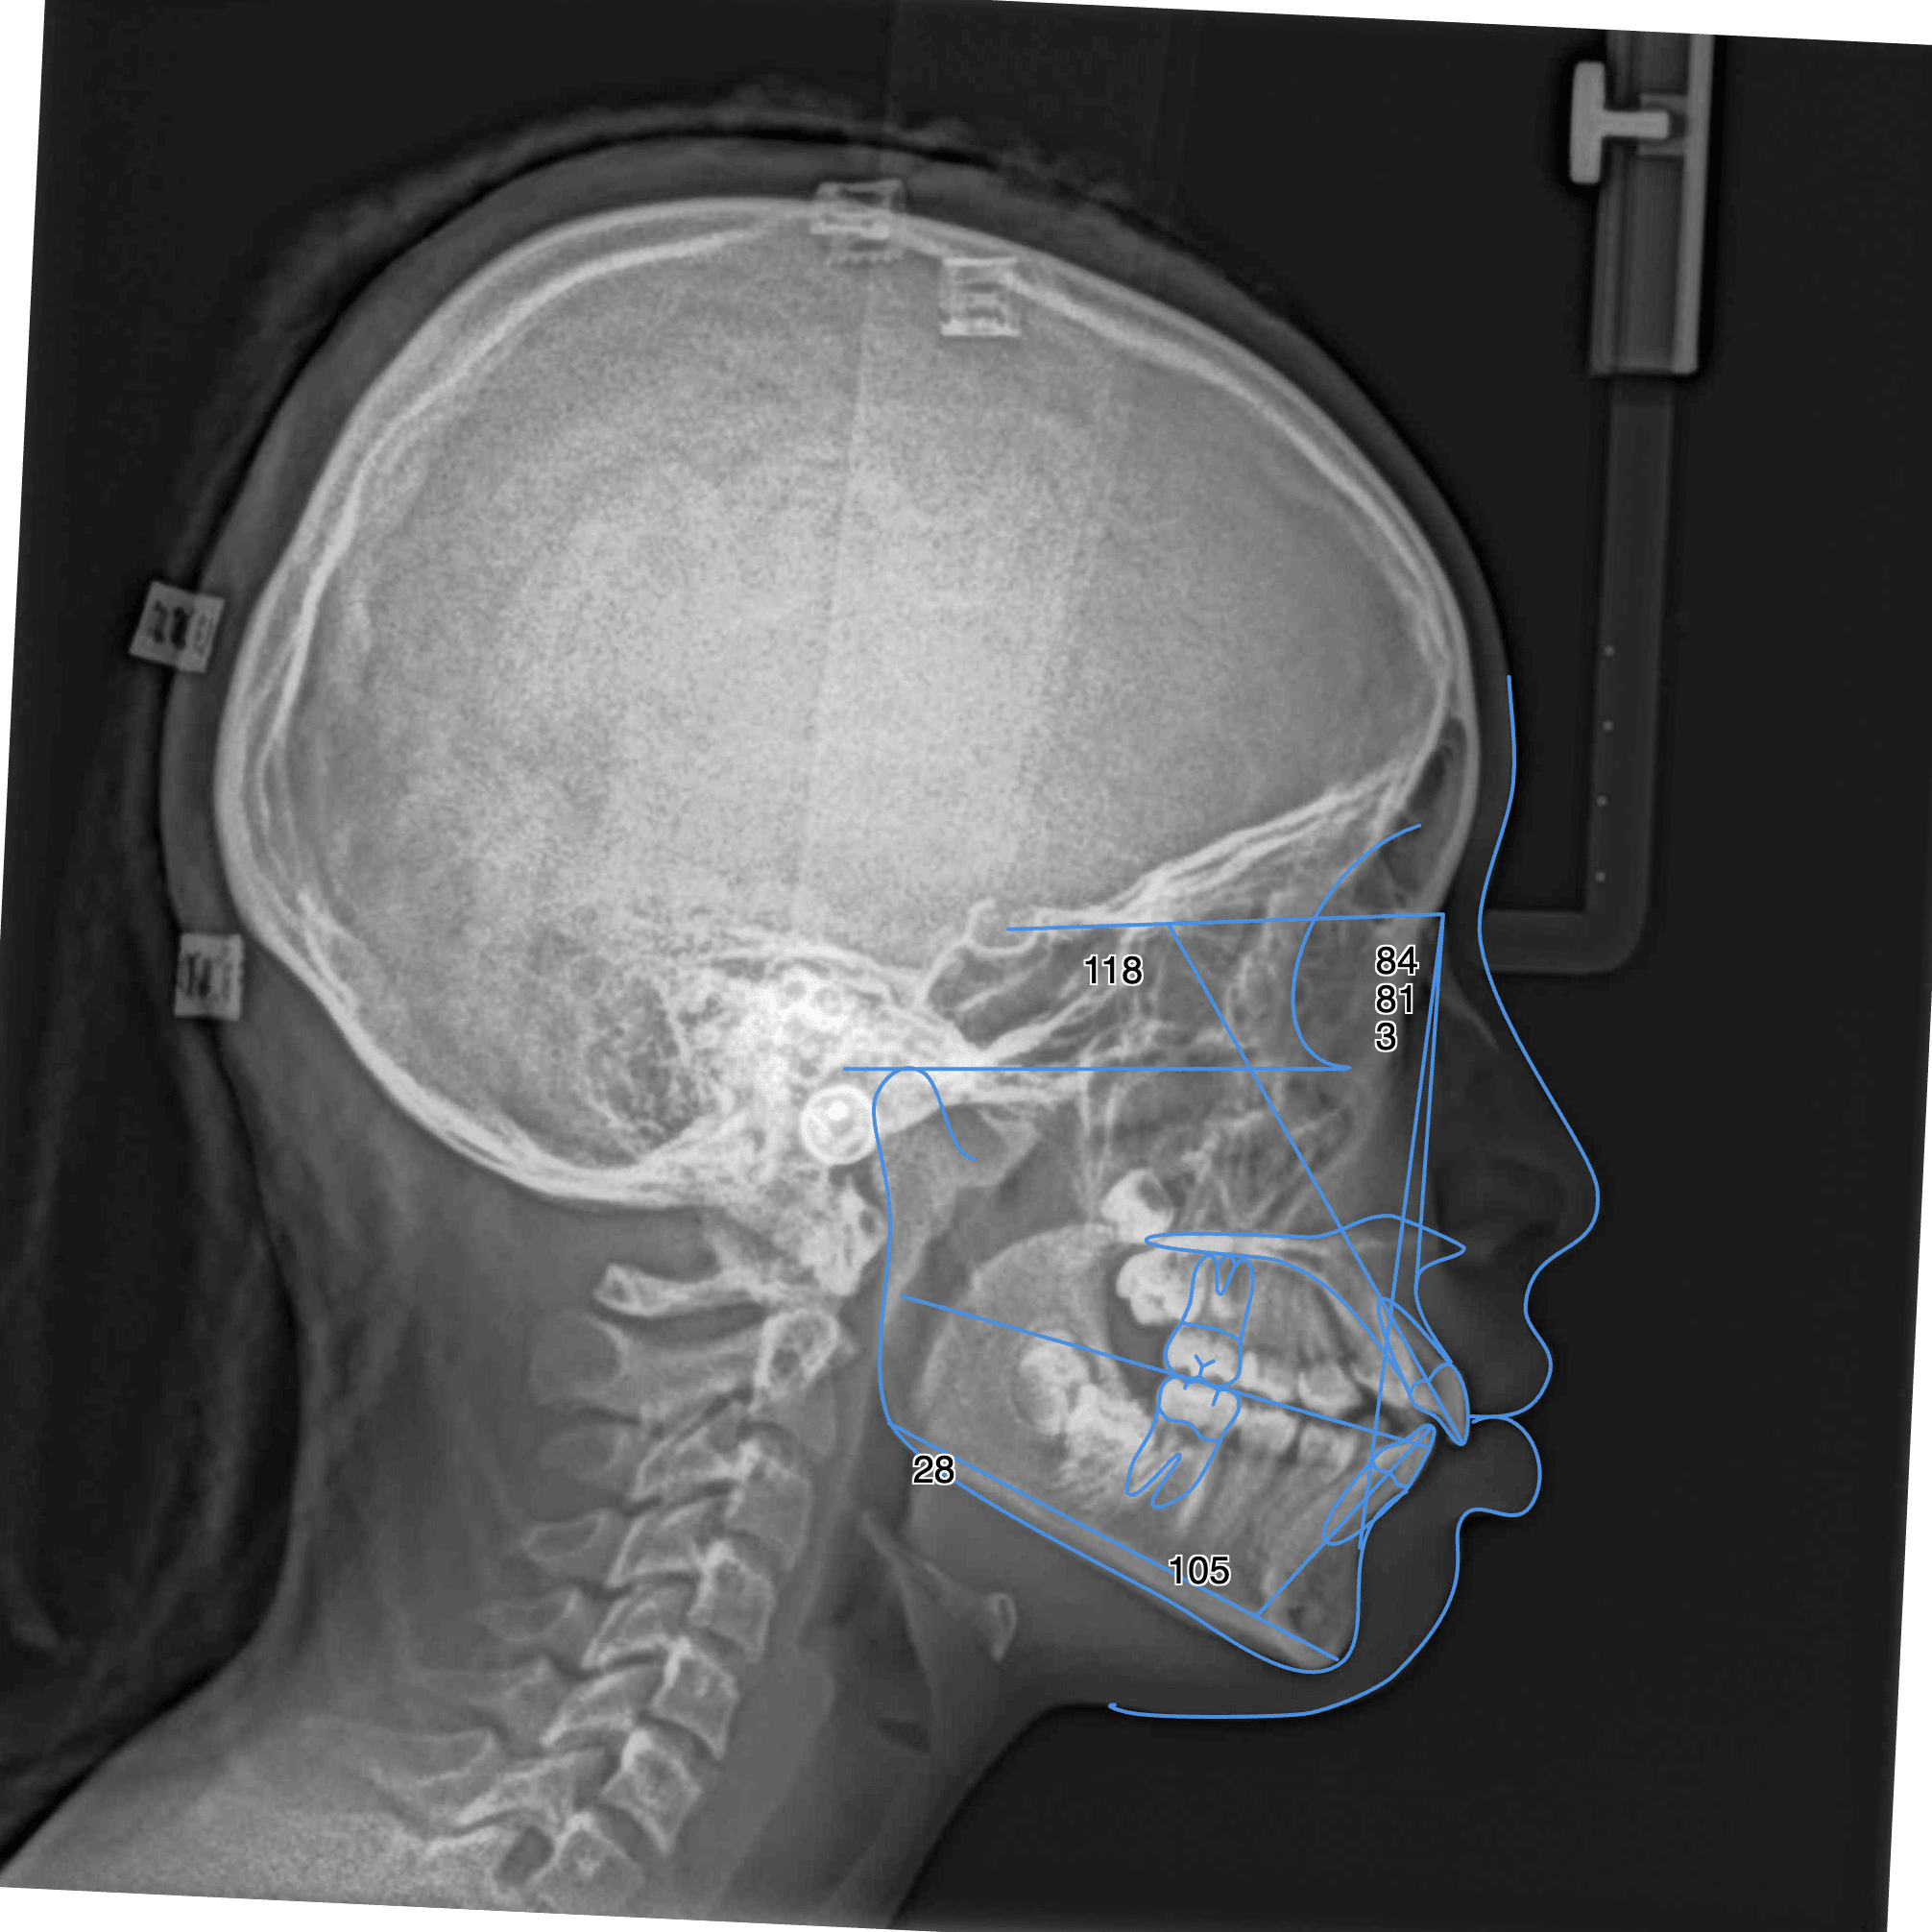

- Téléradiographie de profil : pour analyser la croissance osseuse, l’inclinaison des incisives et les rapports entre les mâchoires.